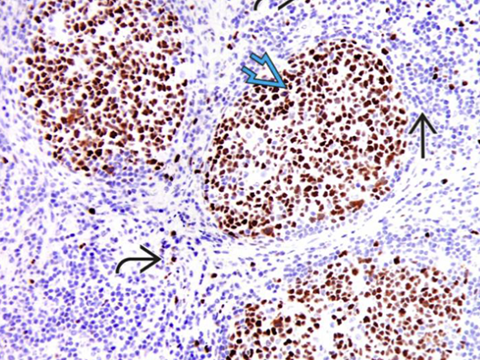

CD3 in reactive follicles. Immunohistochemical stain for the pan T-cell marker CD3 highlights scattered small lymphocytes within germinal centers (solid black line). Many more CD3(+) lymphocytes are noted in the interfollicular region .(open black line) [2]

Immunohistochemical stain for Bcl-6 highlights centrocytes and centroblasts in the reactive germinal centers (open blue arrow) Mantle zone lymphocytes (straight black arrow) are negative; rare or scattered interfollicular lymphocytes (curved black arrow) are positive for Bcl-6. - Ki67 looks similar